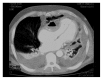

Primary systemic amyloidosis is not easily diagnosed. The immunoglobulin deposits are usually localized in the kidney, heart, and liver. We describe an unusual case of a patient suffering from a pericardial amyloidoma with internal calcifications and air bubbles that compressed the right ventricle and shifted the heart to the left. Since the patient was in shock, urgent pericardiotomy was performed. This site showed PET uptake. A monoclonal component was present. On these findings, differential diagnoses included multiple myeloma and atypical pericardial tuberculosis, whereas a periumbilical fat tissue biopsy demonstrated amyloidosis. A previous Salmonella species infection had most likely stimulated the production of amyloid. The patient received bortezomib/dexamethasone treatment and achieved a good response.